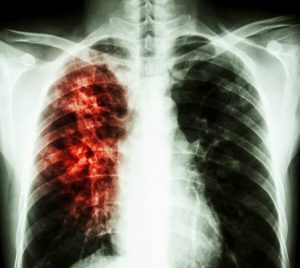

Активный туберкулёз — процесс, при котором у больных бактериологически обнаруживают М. tuberculosis или гистологически выявляют типичные для туберкулёза изменения (гранулёмы), а также характерные для туберкулёза клинико-рентгенологические признаки.

- Инфильтративный туберкулёз лёгких

Рекомендовано также отметить типичные для туберкулёза осложнения: кровохарканье и лёгочное кровотечение, спонтанный пневмоторакс, лёгочно-сердечную недостаточность (ЛСН), ателектаз, амилоидоз, свищи бронхиальные или торакальные и др. По излечении туберкулёза принято описывать остаточные изменения, подразделяемые на малые и большие.